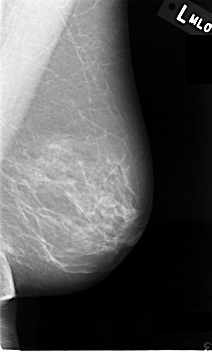

C_0009_1.LEFT_MLO

LEFT_MLO LINES 4576 PIXELS_PER_LINE 2744 BITS_PER_PIXEL 12 RESOLUTION 50 NON_OVERLAY